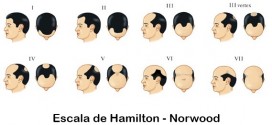

La alopecia androgénica masculina. La causa más frecuente de caída de pelo en los hombres es la llamada alopecia androgénica masculina. El proceso puede empezar en cualquier momento después de la pubertad. En el varón comienza con un retraso de la línea de implantación fronto-parietal (dando lugar a las denominadas entradas). Posteriormente se afecta el área biparietal y el vértex (depilación …